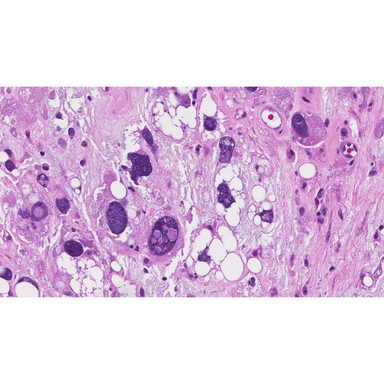

Pleomorphic liposarcoma